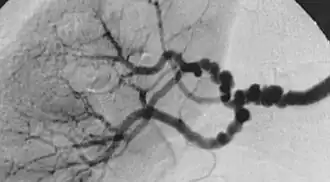

![]() Angiografía en un caso de displasia fibromuscular | ||

La displasia fibromuscular es una enfermedad poco frecuente de causa desconocida que afecta a las arterias de calibre pequeño y mediano provocando disminución de su luz y en ocasiones formación de aneurismas. Los síntomas son variables dependiendo del territorio afectado, cuando causa estenosis de la arteria renal provoca hipertensión renovascular, por el contrario si actúa sobre la arteria carótida causa accidente cerebrovascular por disminución del riego cerebral. El diagnóstico se sospecha por los síntomas y se confirma por angiotomografía computarizada, angiorresonancia magnética o angiografía, donde se observan unos vasos con estrechamientos y dilataciones alternantes según un patrón que se ha descrito como collar de perlas. El tratamiento recomendado es la angioplastia transluminal.[1][2][3]